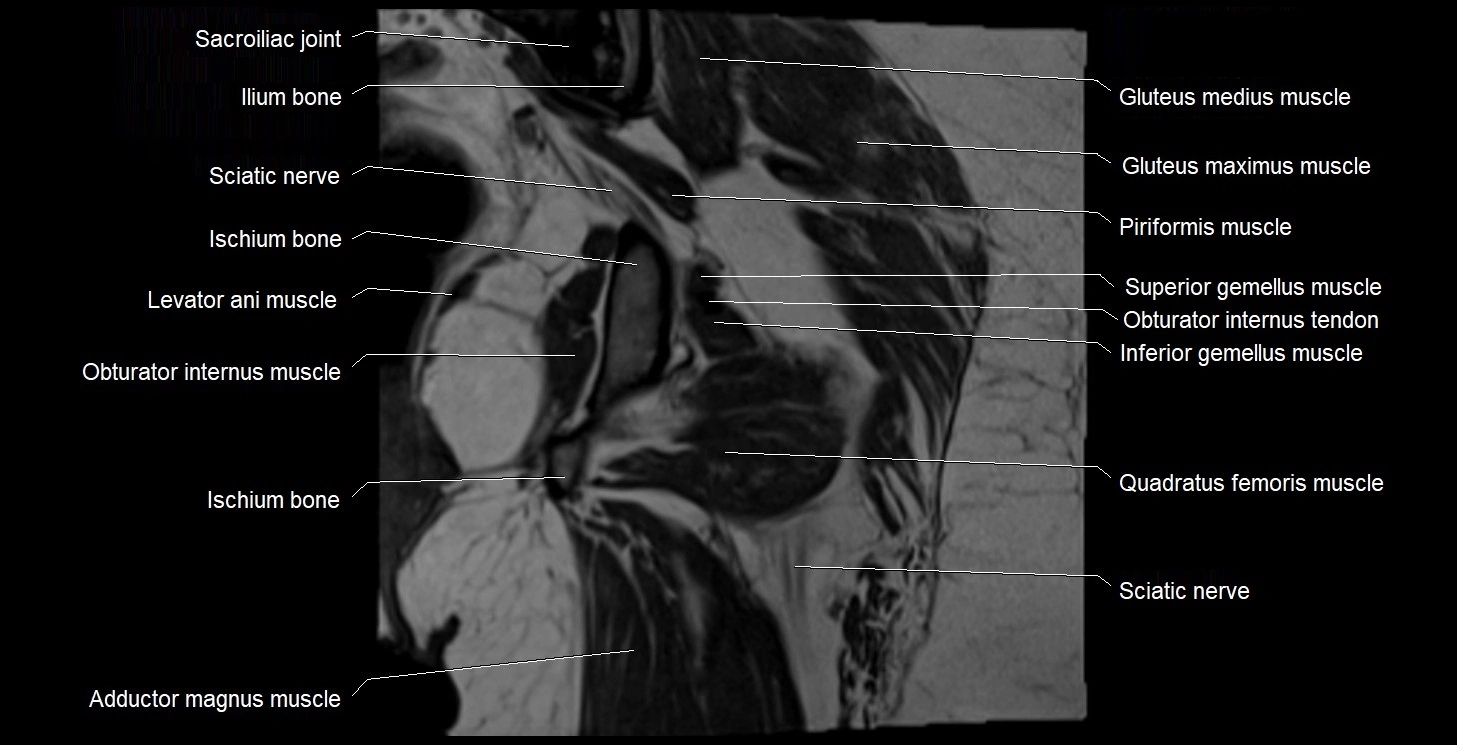

- Adductor magnus muscle

- Gluteus maximus muscle

- Gluteus medius muscle

- Inferior gemellus muscle

- Ischium bone

- Levator ani muscle

- Obturator internus muscle

- Obturator internus tendon

- Quadratus femoris muscle

- Sacroiliac joint

- Superior gemellus muscle